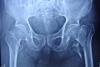

患者男性,63岁,主诉:两年前车祸,造成股骨颈骨折,在当地医院行空心钉内固定术,近1个月出现髋部疼痛,进行性加重,行走障碍。由门诊收入院,诊断为“创伤性股骨头坏死”。入院后查体:体温36.5℃ ,脉搏88次/分,呼吸22次/分,血压143/88mmHg。患者主诉两年前车祸,造成股骨颈骨折,在当地医院行空心钉内固定术,近一个月出现髋部疼痛,进行性加重,行走障碍,现复查,股骨头表面已经有部分塌陷,坏死,内固定钉还未取出,来我院检查,行x先拍髋关节正位片,诊断为“创伤性股骨头坏死” 患者自发病以来精神、食欲良好、因疼痛出现失眠、易醒。患者无不良嗜好,大小便正常。行走苦难生活部分自理。 既往史:既往高血压病史5年。遵医嘱按时服用硝苯地平缓释片,血压维持在135-145/80-90 mmHg。否认冠心病、糖尿病等慢性疾病。否认肝炎结核等传染病史。否认药物过敏史。 专科查体:脊柱生理弯曲大致正常,右下肢较左下肢缩短一厘米。右髋关节呈内旋15度,外旋20度畸形各方向活动受限,屈曲40度,“内收”不能,“4”字实验不能,双下肢肌力肌张力正常。余查体未见异常。 辅助检查: X线示股骨头的形态、结构明显改变,出现大面积不规则塌陷或变平,骨小梁结构变异。髋臼与股骨头间隙消失等。24h动态血压:收缩压98-142 mmHg,平均值118 mmHg;舒张压79-95 mmHg,平均值86 mmHg;平均动脉压134/92 mmHg。心电图:大致正常心电图。 24小时动态心电图提示:窦性心律,心率68-96次/分。 异常化验结果: 总胆固醇5.79mmol/L(